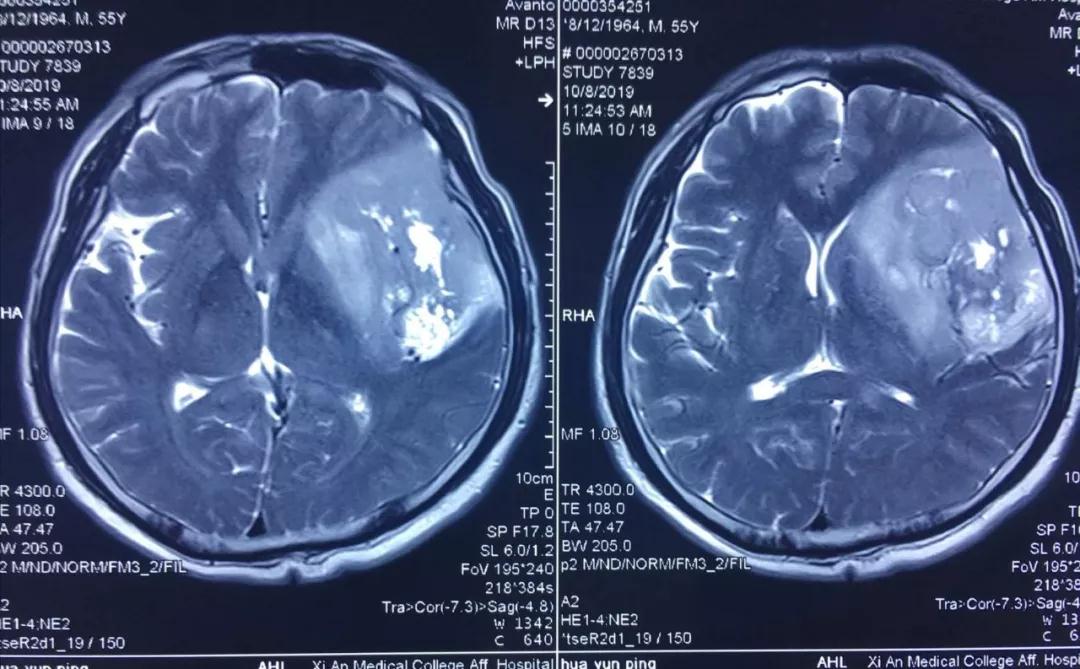

患者李某,今年55歲,因近年出現(xiàn)間歇性面部抽搐,一直未給予重視,近來(lái)發(fā)作頻繁,經(jīng)朋友建議在外院行頭顱核磁檢查,發(fā)現(xiàn)顱內(nèi)巨大占位性病變,病變位于左側(cè)額、顳和深部腦島葉,達(dá)8.5?5.5?3cm,且侵犯語(yǔ)言功能區(qū),顱內(nèi)占位效應(yīng)明顯,中線(xiàn)偏移1cm,且腫瘤已經(jīng)瀕臨腦疝邊緣,如不及時(shí)進(jìn)行手術(shù)干預(yù),隨時(shí)有腦疝可能,危及患者生命。

經(jīng)多方了解后,在朋友的推薦下,患者慕名來(lái)到西安國(guó)際醫(yī)學(xué)中心找到了腦科醫(yī)院高國(guó)棟院長(zhǎng),高院長(zhǎng)帶領(lǐng)以賀世明主任為首的神經(jīng)外科團(tuán)隊(duì),對(duì)患者的病情及治療方案等進(jìn)行討論,憑借多年的臨床經(jīng)驗(yàn),結(jié)合患者影像結(jié)果判斷為顱內(nèi)膠質(zhì)瘤,并建議盡快實(shí)施手術(shù)切除。